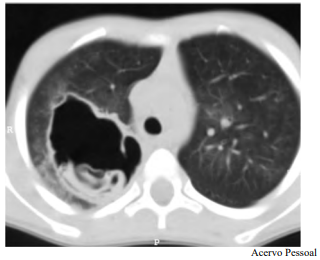

Determinado paciente de 49 anos de idade, morador em zona rural, iniciou com quadro de tosse importante, com piora progressiva, de início há dois meses, associada a alguns episódios de vômica. Refere febrículas na última semana. O paciente é tabagista leve, trabalha com criação de ovelhas e mora em casa com cachorros e gatos. Nega viagens internacionais recentes. Não foi encontrada nenhuma alteração no exame físico. Verificaram-se FC = 80 bpm, FR = 20 irpm e SatO2 = 99% em ar ambiente. A tomografia de tórax apresenta uma lesão cística de paredes espessas e conteúdo heterogêneo em seu interior, conforme representado na imagem a seguir.

Tendo em vista esse caso clínico e os conhecimentos médicos correlatos, julgue o item a seguir.

A doença apresentada é diagnosticada facilmente em pacientes com lesões císticas pulmonares e teste sorológico positivo, que moram em zonas endêmicas, como o paciente do caso clínico.